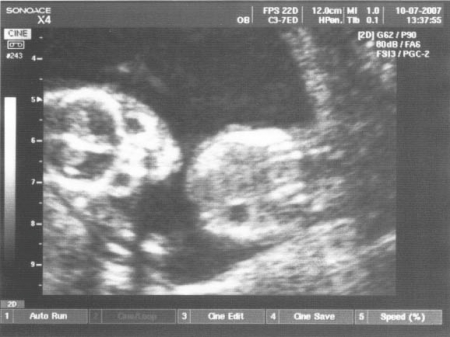

15. týden těhotenství pokračuje rychlý růst tělíčka plodu do délky. Na konci 4. měsíce tvoří hlavička asi třetinu celkové délky plodu. Mozek pokračuje ve svém vývoji. Na jeho povrchu se již vytvořila tenká vrstvička šedé hmoty.

Na povrchu hlavičky začíná být patrná část porostlá vlasy. Na okrajích očních víček se objevují jemné řasy. Oční víčka jsou stále srostlá.

Boltec ouška má už v podstatě definitivní tvar.

Celé tělíčko je pokryté velmi tenkou pokožkou. Jsou v ní již založeny všechny obvyklé vrstvy. Objevují se první buňky, které obsahují pigment. Jejich množení patří k faktorům, které v budoucnu ovlivní zbarvení kůže. Celý povrch těla je pokryt velmi jemnými kožními chloupky (lanugo).

V 15. týdnu těhotenství plod měří od temene k zadečku 9 - 10 cm, váží asi 40 – 50 g.